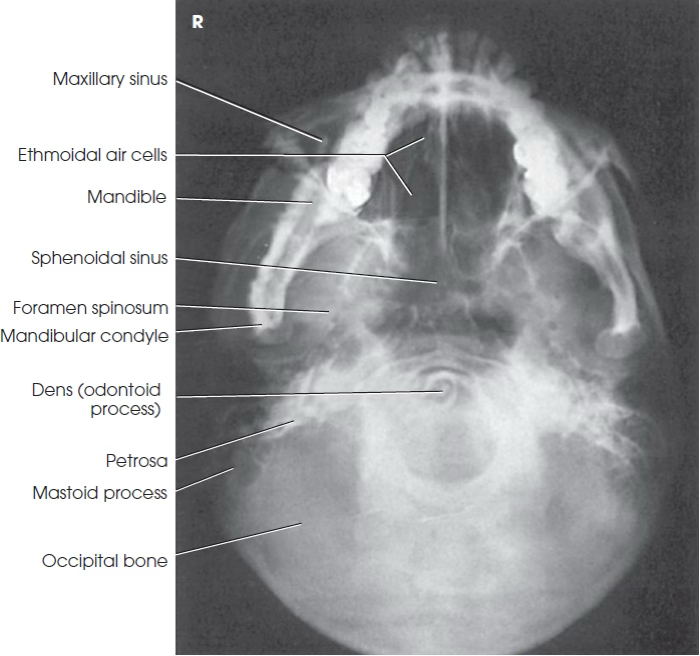

SMV

SMV Skull part position

Extend neck placing IOML parallel with IR

SMV Skull central ray

Perpendicular entering 1 inch anterior to EAM MSP

SMV Skull evaluation

Mandibular condyles anterior to petrous pyramids